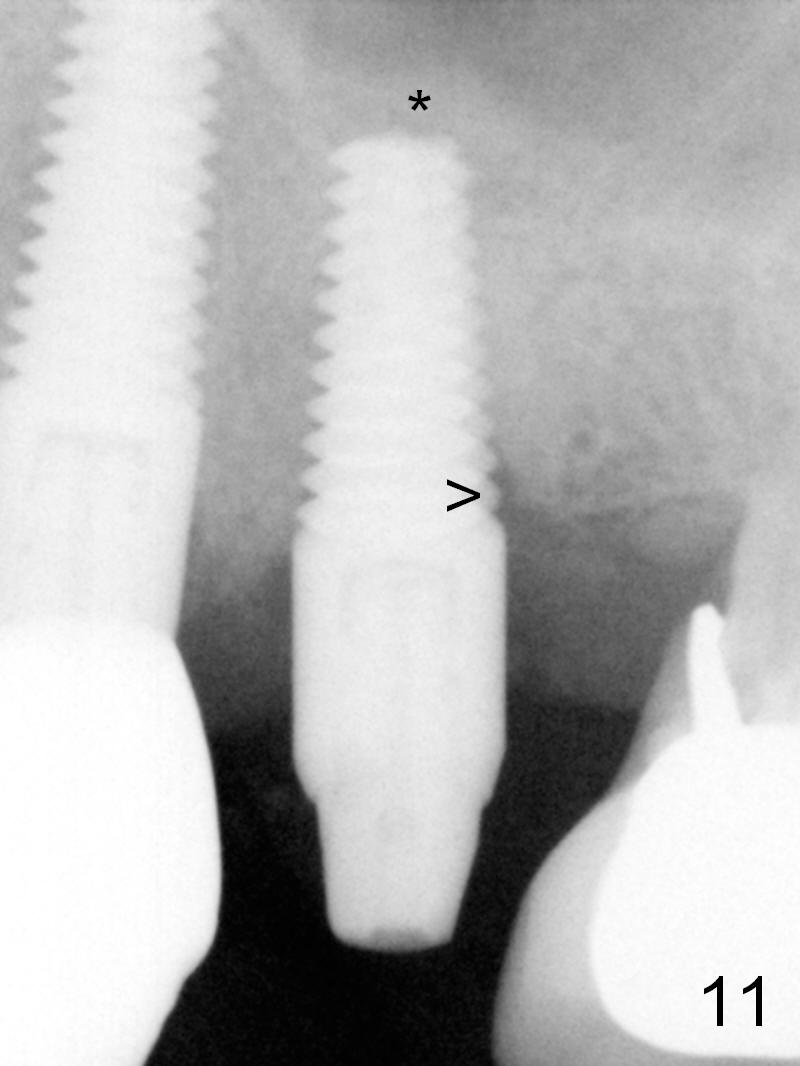

The distal threads appear not covered by the bone 2.5 months postop (Fig.11 >). His oral hygiene is excellent with healthy gingiva around the implant when the permanent crown is cemented. Panoramic X-ray is taken 3 years and 1 year 5 months post cementation for #12 and 13, respectively (Fig.12). The bone density around the implant at #13 increases 2 years 6 months post cementation (Fig.13 *). The bone density of the sinus lift (Fig.14,15 *) is essentially the same as that of the bone buccal (B) and palatal to the implant 4.5 years post cementation. The upper left panel is a 3D view from the sinus.